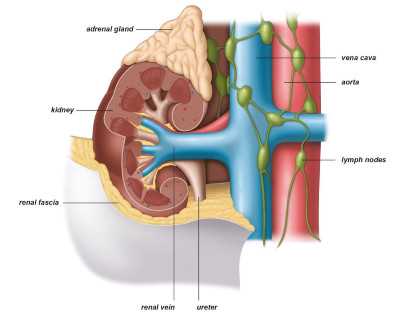

Οι νεφροί είναι δύο όργανα σε σχήμα φασολιού στο πίσω μέρος της κοιλιάς (οπισθοπεριτόνεο) που φιλτράρουν το αίμα από βλαβερές ουσίες αποβάλλοντας ούρα. Είναι σημαντικοί για λειτουργίες, όπως η ρύθμιση της αρτηριακής πίεσης, η παραγωγή κυττάρων του αίματος και της διατήρησης της υγείας των οστών (Εικ. 1).

Εικ. 1: Ο νεφρός, οι φλέβες και οι αρτηρίες του